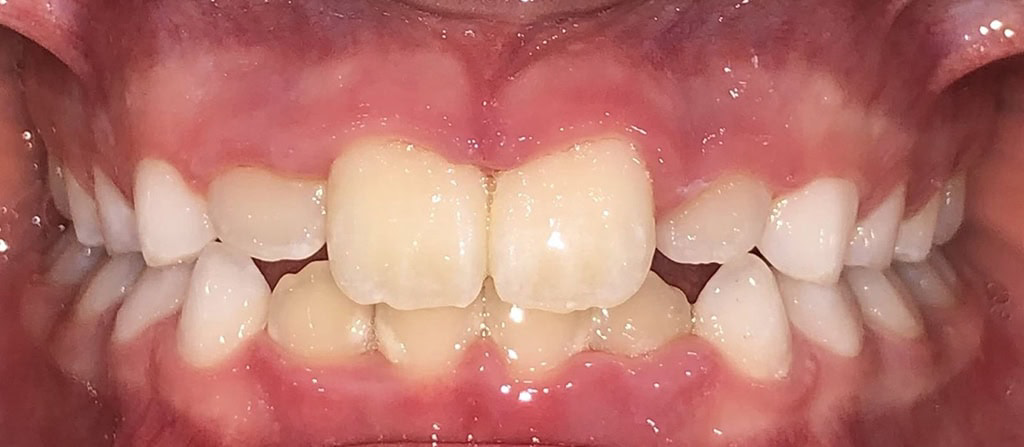

Actual Patient: Victoria

Img Before 1 1 Img After 1 1

Severe Crowding, Narrow Jaws, Severe Deep Bite

image 1 after img

Treatment Time:

8 months

Front View

Top View

Right & Left Sides